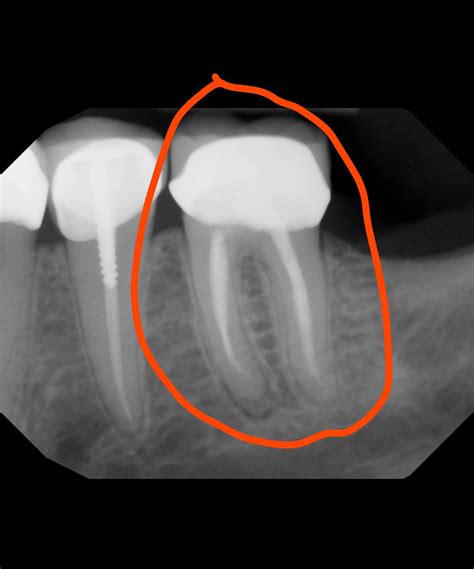

Professional dental intervention is the only way to treat a root abscess effectively. A dentist will typically perform an X-ray to confirm the diagnosis and determine the extent of the infection. Treatment options generally include:

A root abscess is a localized collection of pus caused by a bacterial infection at the root of a tooth. This infection typically occurs when bacteria enter the tooth through deep cavities, fractures, or failed dental work, reaching the pulp—the inner part of the tooth that contains blood vessels and nerves. As the body attempts to fight this infection, it sends white blood cells to the area, resulting in the formation of pus. If this pus cannot drain, it forms an abscess, leading to intense pain and potentially serious complications.